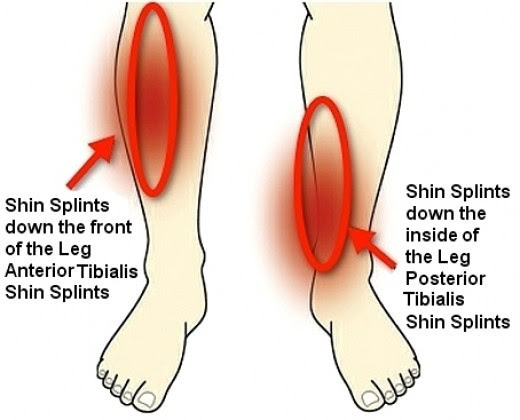

Shin splints

Shin splints is an inflammation of the muscles, tendons, and bone tissue around your shinbone. Pain typically occurs along the inner border of the tibia, where muscles attach to the bone.

Shin splints are a common exercise-related problem.

Shin splints usually develop when the muscle and bone tissue in the leg become overworked by repetitive activity, often in response to sudden changes in physical activity. These can be changes in frequency, such as increasing the number of days you exercise each week. Changes in duration and intensity, such as running longer distances or hills.

Other factors that contribute to shin splints include: